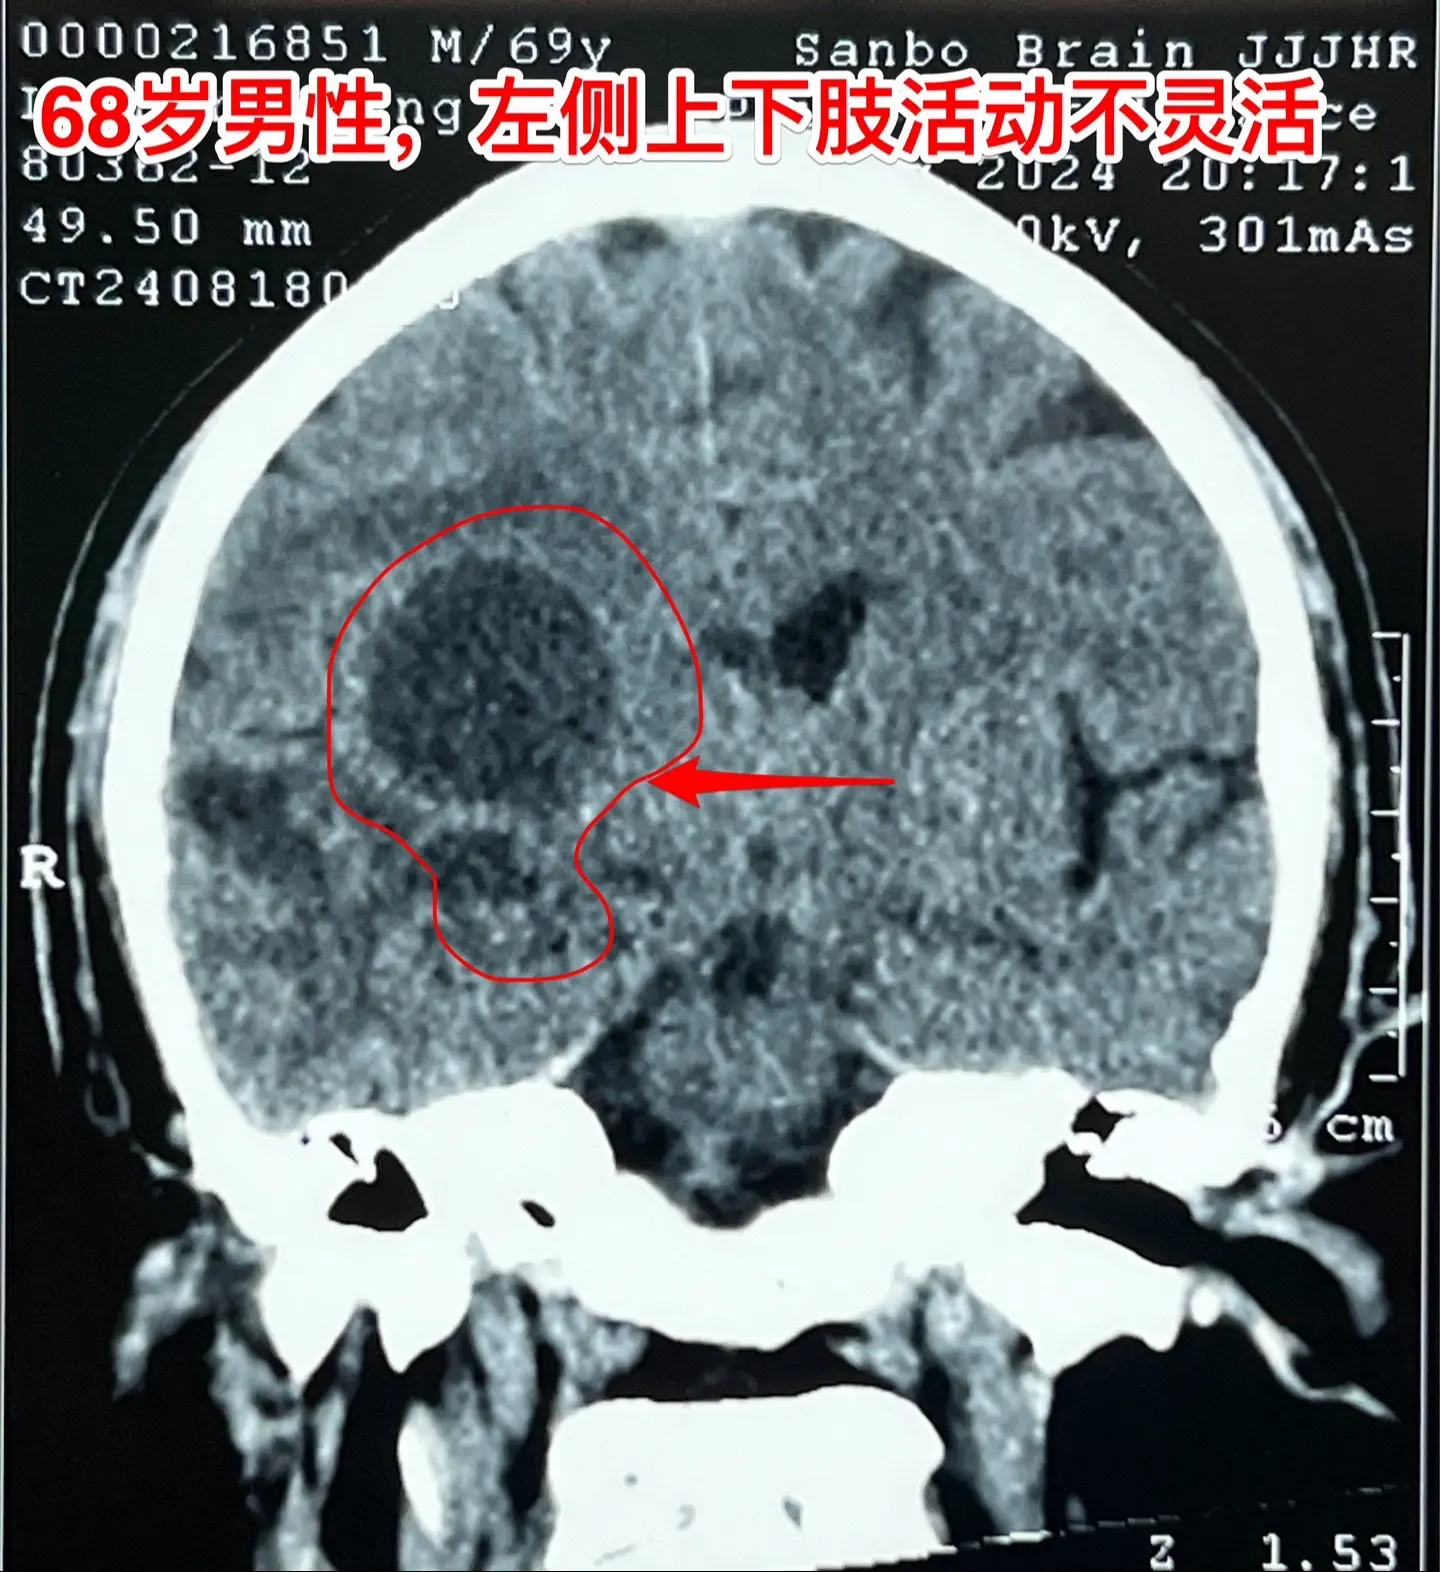

老人擀饺子皮的质量下降了,原因是什么?68岁的唐山市老人,擅长擀饺子皮、包饺子,平时擀出的饺子皮中央稍厚、四周均匀薄。然而近期他擀出的饺子皮形态不规整,厚薄一致,与平时的水准大相径庭,是什么原因呢?而且家人发现他穿鞋系鞋带动作又慢又笨拙!跟平时完全不一样。 病人的女儿在北京当医生。 到医院去检查脑部磁共振就发现脑部长了一个瘤。这个瘤位于左侧颞叶-基底节区,压迫内囊区域,虽然没有造成明显的偏瘫症状,但是也造成了左侧上下肢活动不灵活。 8.16到我这里来住院,8.23作了手术,术中的快速冰冻病理提示高级别神经上皮肿瘤,即胶质瘤的一种。 手术后老人没有出现明显的偏瘫症状。 这样的肿瘤单纯作手术是不够的,还需要作放疗、化疗。